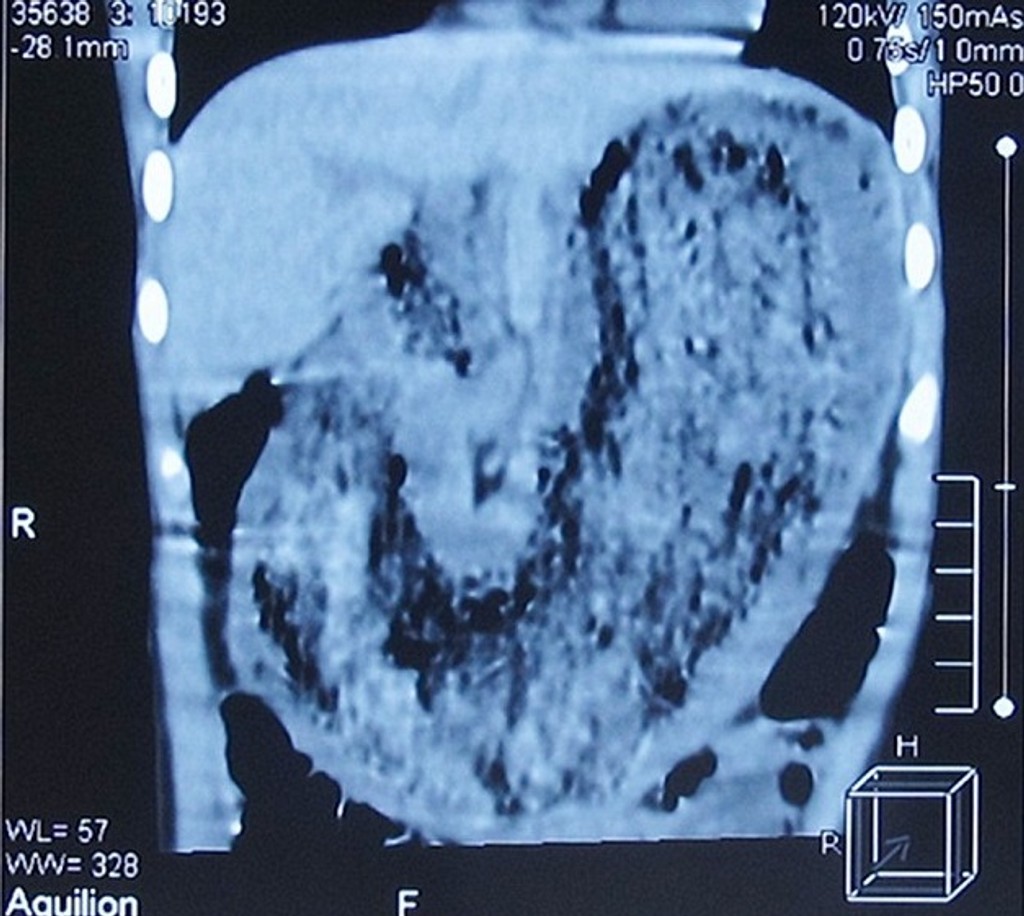

Ten vďaka CT vyšetreniu našiel v jej žalúdku obrovský nález. Školáčku sa rozhodli ihneď operovať a po úspešnom zákroku takmer neverili vlastným očiam. Dievčatko malo v žalúdku obrovskú guču vlasov, nechtov a látky.

Mála Číňanka musela dlhodobo jesť vlastné vlasy, hrýzť si nechty a priznala sa, že ožúvala aj svoje oblečenie. Hrozný nález tohto všetkého vážil takmer dve kilá.

„Vlasy a nechty musela jesť dlhšiu dobu. Objekt bol tak veľký, že jej bránil prijímať ďalšiu potravu," povedal pre britský denník DailyMail miestny doktor Zhang Shufeng.